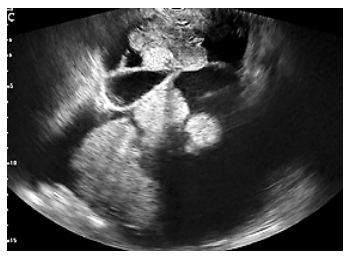

Analise a imagem a seguir.

Com uma tumoração com essas características, em ultrassonografia endovaginal de uma mulher com 65 anos de idade é possível fazer a hipótese diagnóstica de